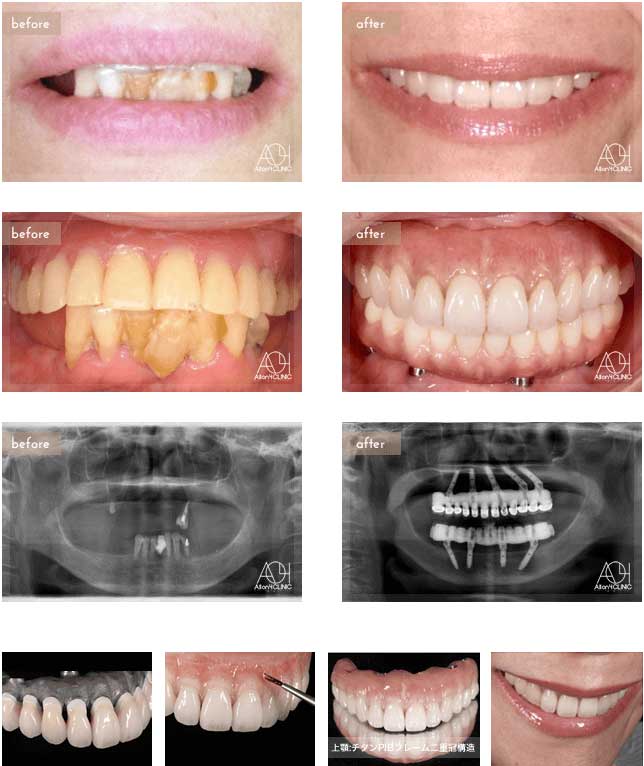

Treatment : All-on-4 non gum

- Upper All-on-4

- Lower implant

Age : 42 Sex : 女 Y.R

| 主訴 | 歯がボロボロなのは分かっているが、時間的な余裕が無いことと歯科に対する恐怖心から、悪いままの状態を放置してしまった。人前でおもいっきり笑いたいので意を決して来院。 |

| 治療内容 | ガイデッドサージェリーにてインプラント埋入。歯槽骨が残っていたため歯冠形態のみ(ガム無し)の補綴 |

| 治療費(総額) | ¥3,500,000(税抜) 『モニター割引適用』 |

| リスク | 治療後の口腔管理が不適切な場合、埋入したインプラント周囲に感染・炎症を起こし、脱落する可能性がございます。 |